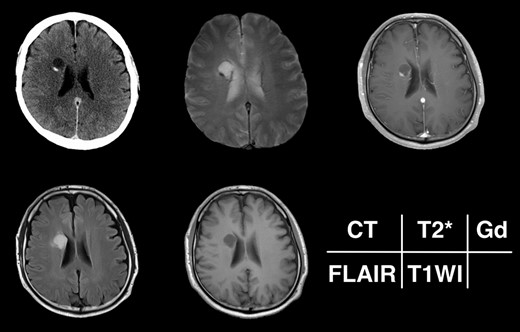

Given the absence of neurological symptoms, the patient was followed conservatively. After a follow-up period of 10 years, the lesion started to increase in size from 10 to 18 mm, accompanied by worsening of headaches. MRI revealed that the increased size of the lesion was attributable to an enlargement of the cystic component and the mural nodule (Fig. 1). A cystic mass with a gadolinium (Gd)-enhancing cyst wall and mural nodule were present. Signal intensity of the cystic component was high on T2-weighted imaging and fluid-attenuated inversion recovery (FLAIR) imaging. The cyst wall and nodule showed low signal intensity on T2*-weighted imaging (Fig. 2). Surgical removal was performed via a trans-cortical approach achieving gross total removal. The cystic component was covered with a transparent thin membrane containing clear yellow fluid, while the mural nodule comprised white, tough tumorous tissue. The lesion showed no invasion into the lateral ventricle. The postoperative course was uneventful, with no complications. No headache and no sign of recurrence have been seen, as of 13 months after surgery (Fig. 2).

Radiological appearance of the lesion on CT and MRI. The lesion appears as a hypodense cyst with hyperdense nodules in the periventricular region on CT. Both the cystic wall and nodule show signal hypointensity on T2*-weighted images and Gd-enhancement on contrast-enhanced T1-weighted images. The cyst is hyperintense on FLAIR and hypointense on T1-weighted images.